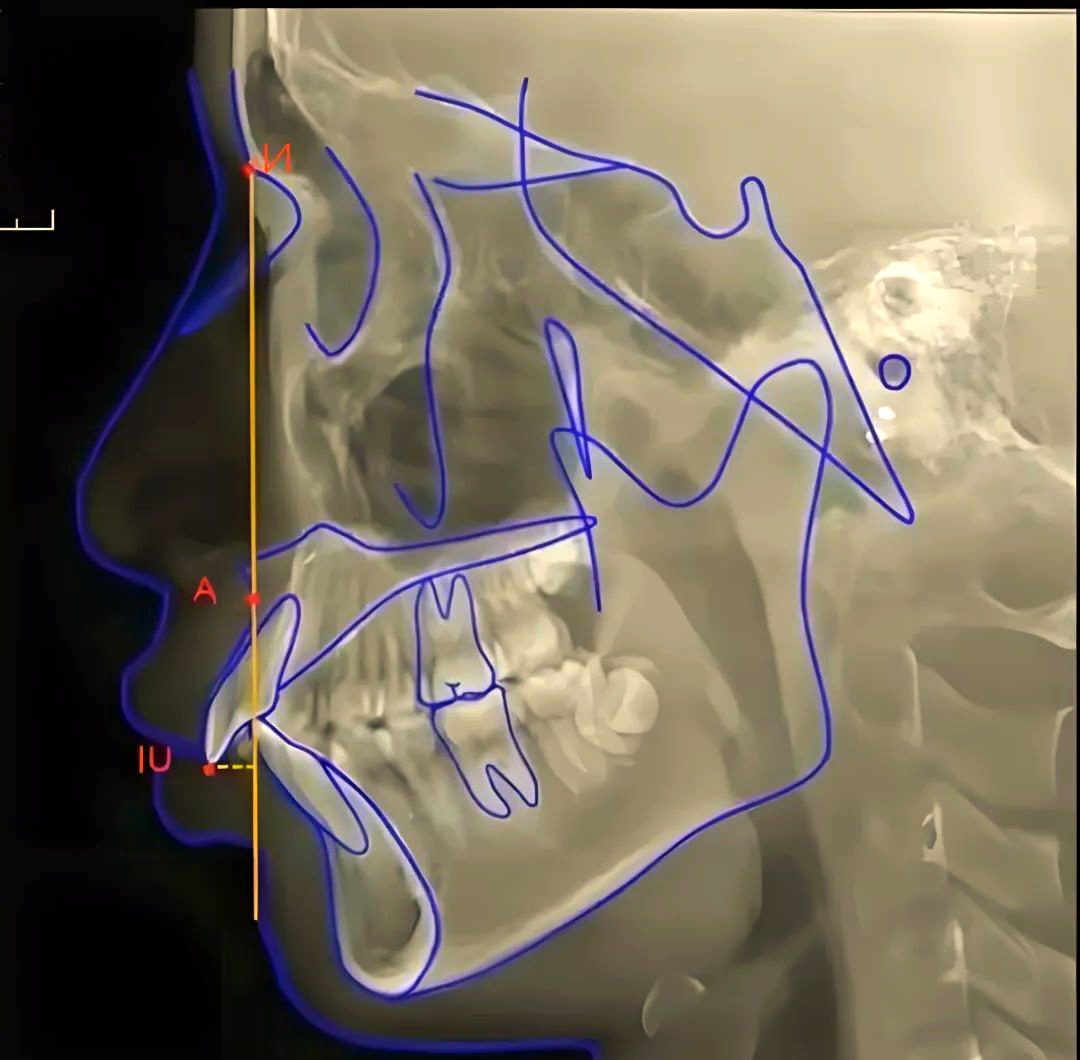

头影测量a点

正畸头影测量常用标志点详解

头影测量中如何准确找到标记点